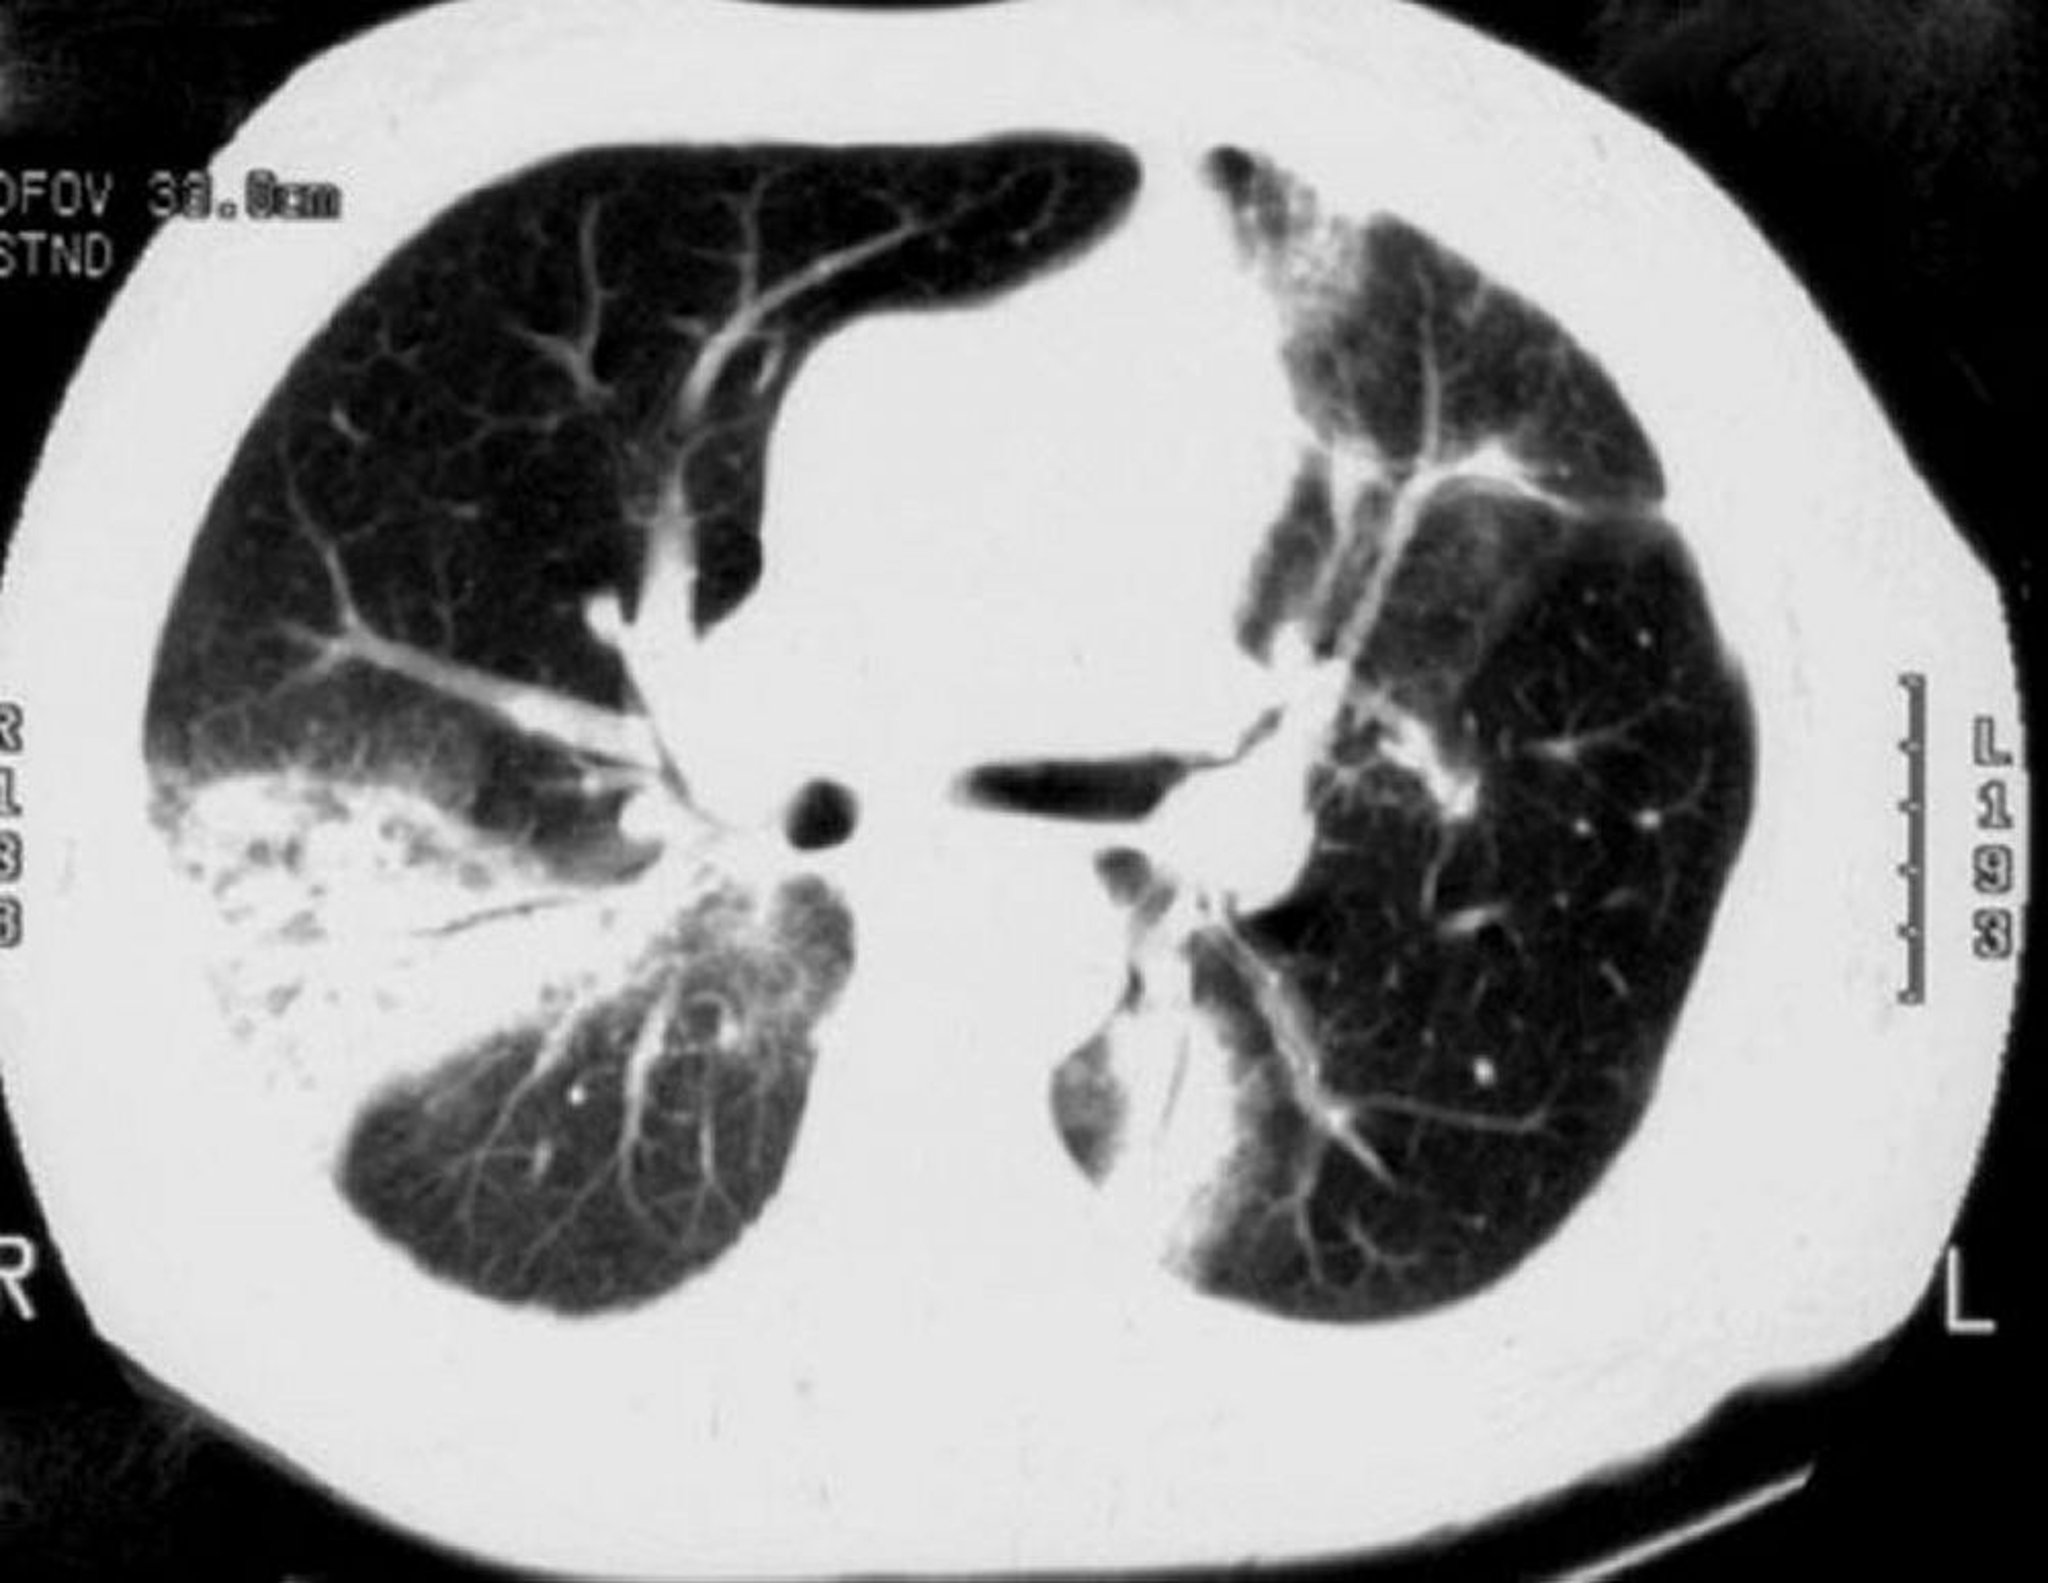

Pneumonia em organização criptogênica

TC de alta resolução mostra consolidação esparsa dos espaços aéreos, opacidades em vidro fosco, pequenas opacidades nodulares e espessamento e dilatação da parede brônquica (broncograma aéreo).

Imagem cedida por cortesia de Talmadge E. King, MD.